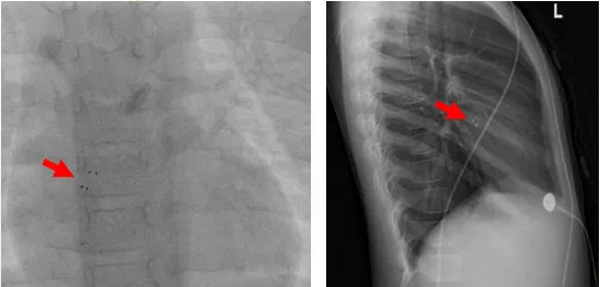

第1例手术患者为一名5岁6月、患有室间隔缺损的儿童,超声心动图提示膜周部室间隔缺损约4mm,缺损上缘距离主动脉右冠瓣无残端,右冠瓣轻微脱垂,若采用传统的金属封堵器介入封堵,术后发生心律失常、主动脉瓣返流等并发症的几率偏高。第2例手术患者为一名8岁伴反复头痛1年、患有卵圆孔未闭的儿童,经药物治疗无效,超声心动图提示卵圆孔未闭2mm。

室间隔缺损封堵